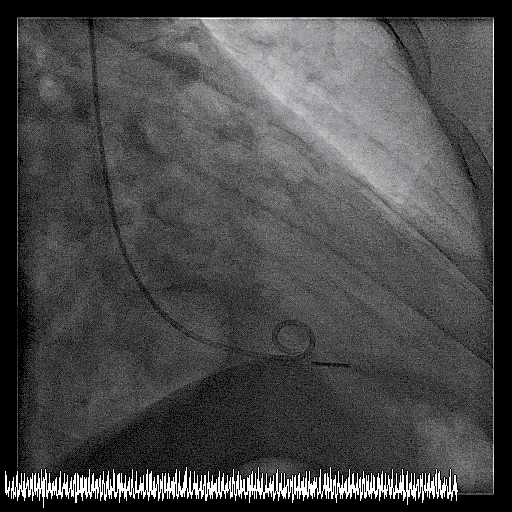

4. The right coronary artery is dominant and occluded proximally.